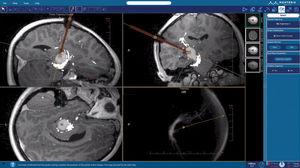

software para imágenes médicasNeuroBlate ® SoftwareTM NeuroBlate ®

... NeuroBlate Fusion™ El software permite a los neurocirujanos planificar, entregar y monitorear la termoterapia robótica con láser guiada por RMN * Formar con precisión los márgenes de ablación para garantizar la precisión quirúrgica * ...